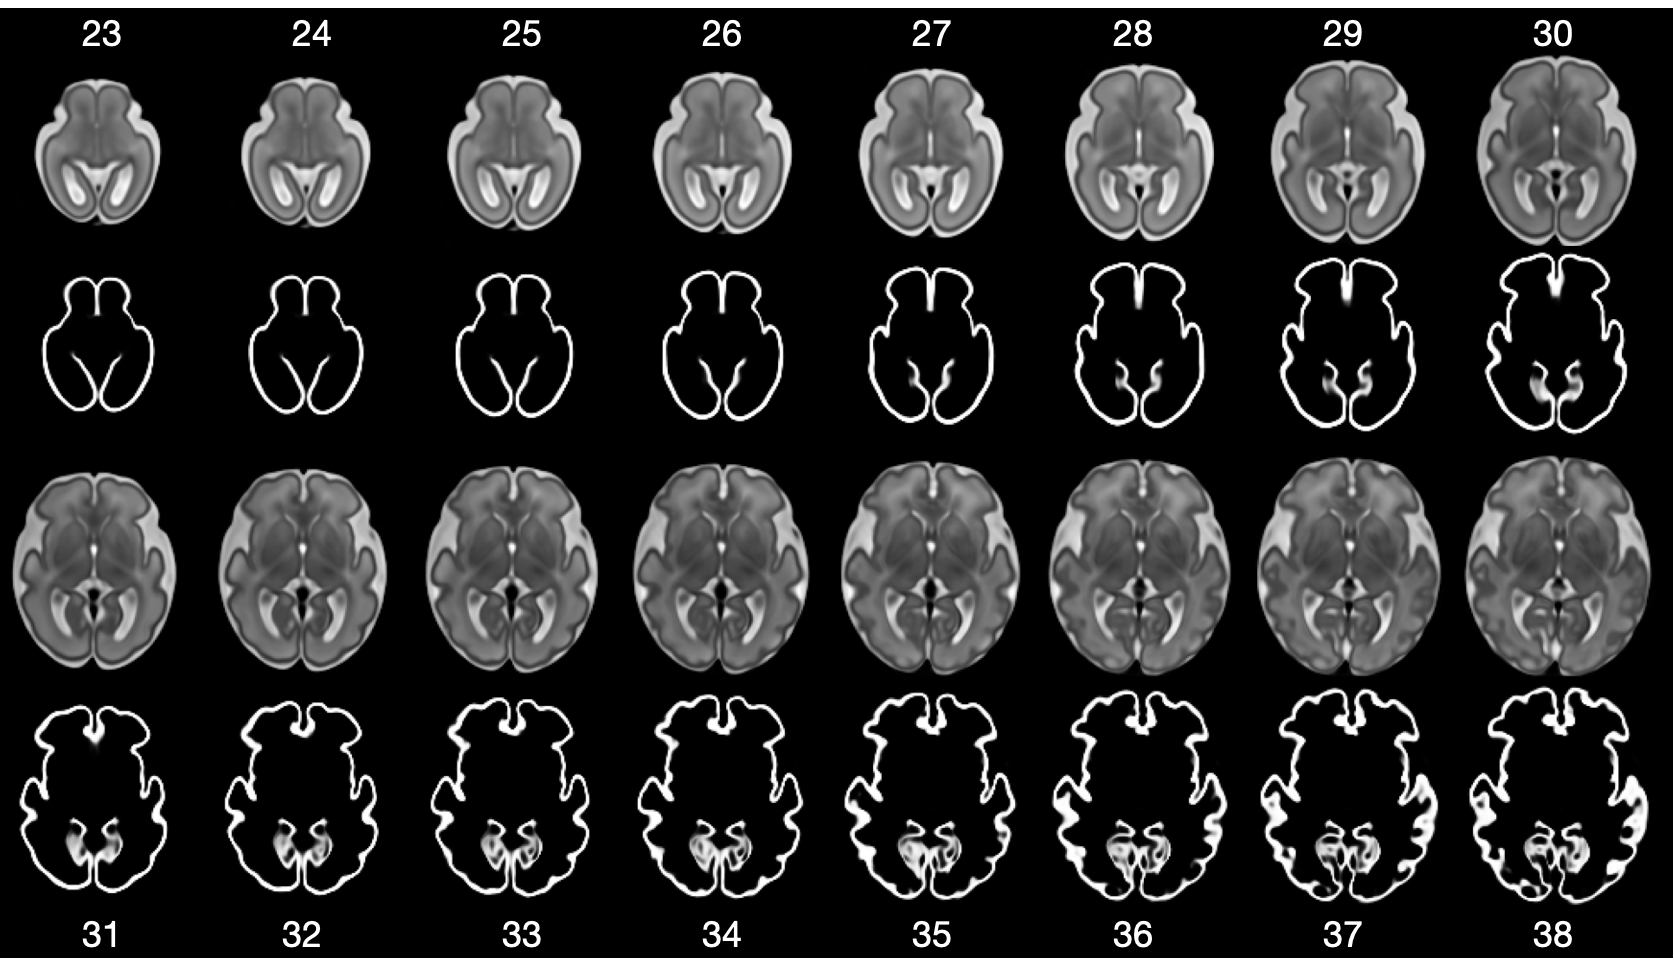

Refer to caption

Figure 4: Temporal fetal brain atlas from 23 to 38 GA with corresponding probability maps of the cortical grey matter.

CINA implicitly represents a spatial- and time-continuous atlas. Contrary to 3D image based atlases that are only available for fixed, discrete time points and resolution, CINA can generate atlases for any time point and resolution. Fig. 4 presents a temporal atlas generated with CINA for GA 23 to 38. Moreover, CINA can generate the temporal atlases while simultaneously conditioning on learned anatomical characteristics, visualized by Fig. 2 b+c) for LV volume and Giryfication Index of the cortex for a specific time point.